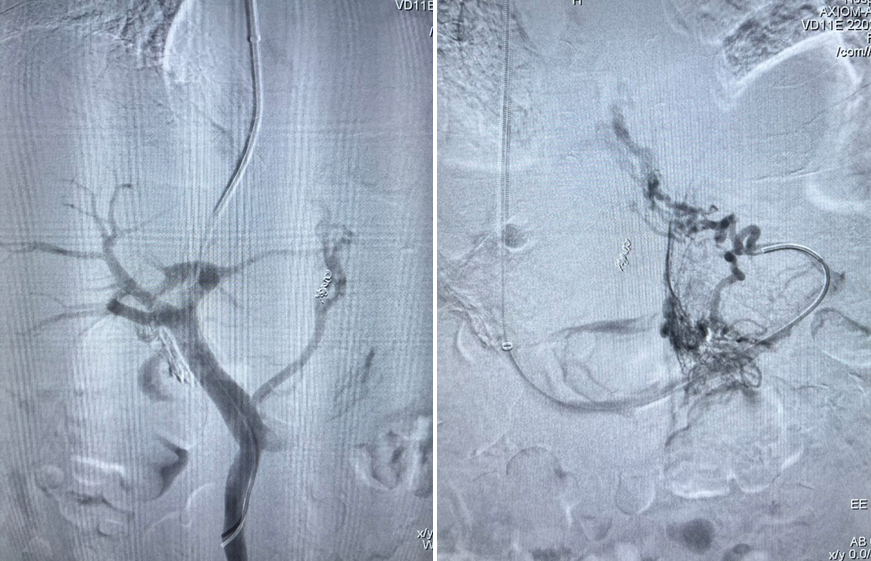

栓塞材料与再干预技术

栓塞剂从早期的泡沫硬化剂、无水酒精、弹簧圈,发展到如今的生物组织胶,止血更彻底;

泡沫硬化剂—无水酒精—弹簧圈—生物组织胶

Viatorr覆膜支架的应用

针对分流道再狭窄或再出血,创新应用平行支架技术,并通过体外模拟验证支架扩张可行性;

平行支架技术

TIPS术后再出血,胃底静脉栓塞+平行支架

经皮经肝导丝引导穿刺门静脉左支,血管塞栓塞异常分流道及胃底曲张静脉

弹簧圈联合血管塞+组织胶栓塞异常分流道